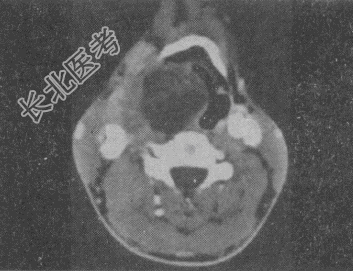

- 单项选择题男,41岁, 右侧咽部不适2年余,有异物感, 声音嘶哑,CT如图, 最可能的诊断是

A、颈动脉体瘤

B、咽旁转移瘤

C、咽旁淋巴瘤

D、小唾液腺瘤

E、咽旁神经鞘膜瘤